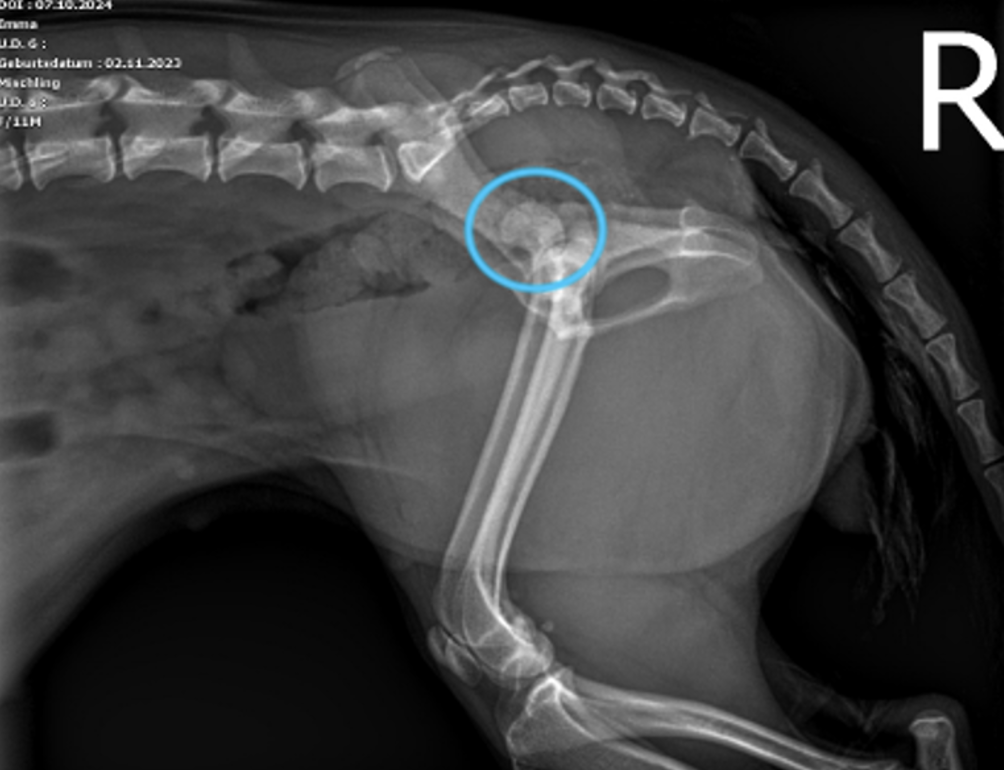

Anbei die Röntgenbilder der Hündin Gina. Gina ist eine weiblich kastrierte 1-jährige Mischlingshündin und wurde bei uns aufgrund einer Lahmheit nach Trauma vorstellig. Welche Pathologien erkennen Sie und welches weitere Vorgehen empfehlen Sie?

Vielen Dank für die Zusendung der Röntgenbilder. Uns liegt eine links laterale Aufnahme des Thorax vor. Hierbei ist die Herzschattenkontur, die Lungengefäße, das Lungenparenchym, die mediastinalen Strukturen, der Pleural Raum und die sichtbaren kranialen abdominalen Strukturen ohne besondere Befunde. Das Zwerchfell ist intakt und der abgebildete Bewegungsapparat ist normal, ohne Hinweis auf Frakturen.

Der rechte Femurkopf ist vollständig aus dem Acetabulum luxiert und nach kranial und dorsal verschoben (blaue Kreise). Die Weichteile des linken Femurs sind geringgradig verdickt. Im linken lateralen Aspekt der abdominalen Wand ist eine minimale Luftansammlung erkennbar. Beidseits sind die Coxofemoralgelenke geringgradig nach außen rotiert, welches eine laterale Positionierung der Patellae verursacht. Im rechten Kniegelenk befindet sich die Patella jedoch in medialer Position (blauer Pfeilkopf). Es ist unklar, ob ob diese traumatisch oder rasse-bedingt entstanden ist und welcher Grad der Patellaluxation vorliegt. Die sichtbaren caudalen abdominalen Organe sind ohne besonderen Befund.

Es handelt sich um eine akute, geschlossene, monostotische, segmentale Fraktur des rechten Os pubis, eine kraniodorsale Luxation des linken Femurs, eine mediale Luxation der rechten Patella und eine geringgradige Weichteilschwellung des linken Oberschenkels.